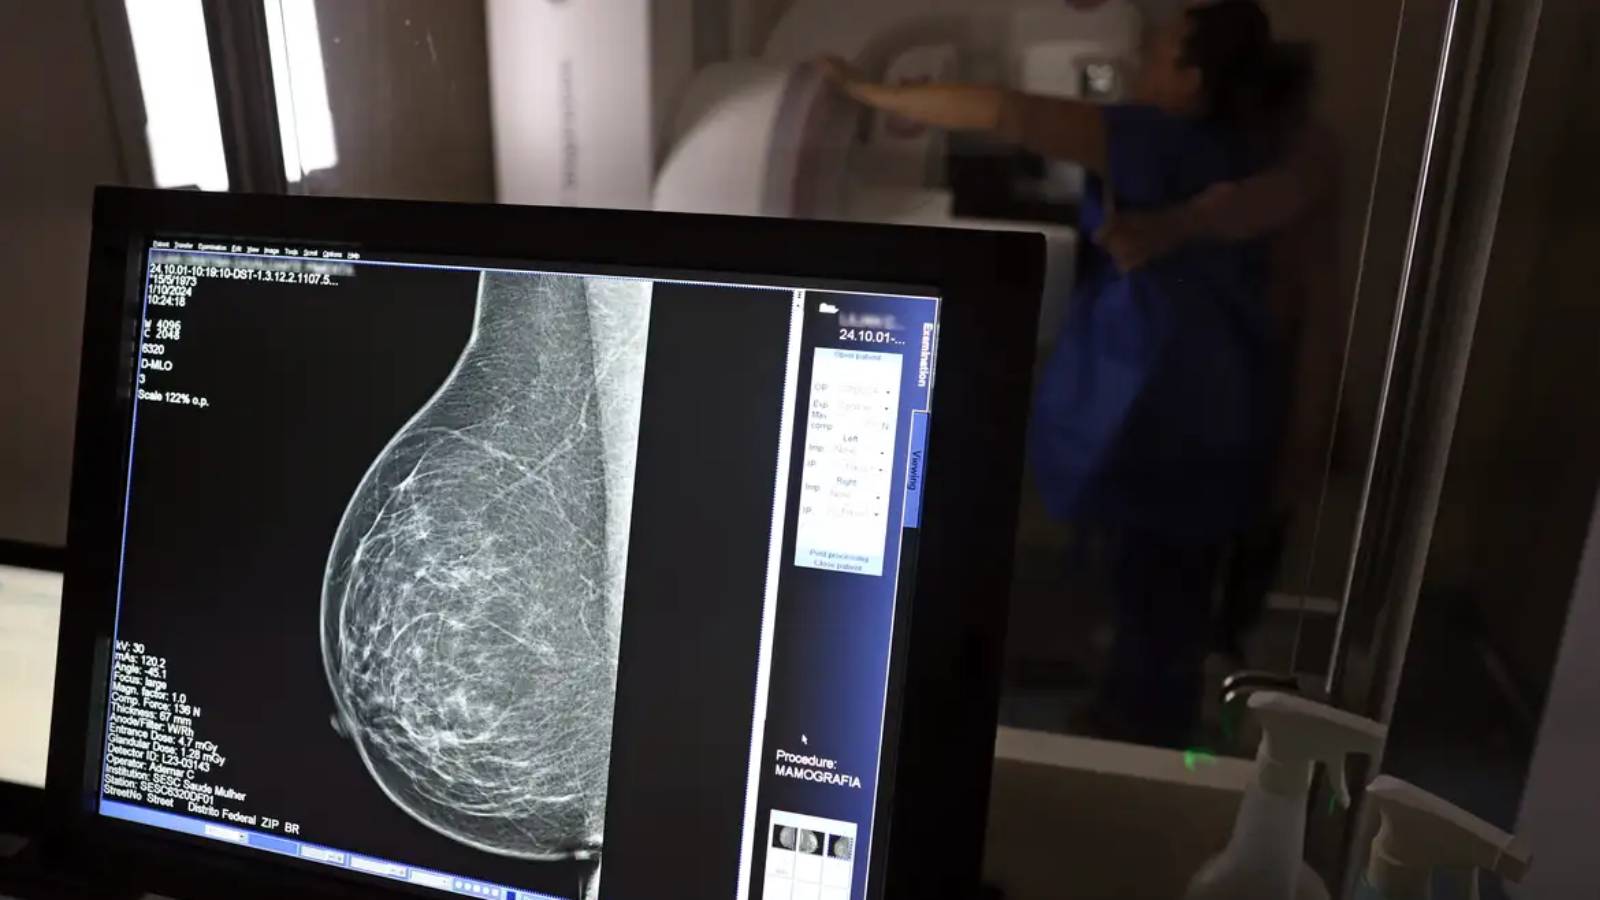

Norma determina que o exame será garantido a todas as mulheres a partir dos 40 anos, conforme diretrizes do Ministério da Saúde

Assinada pelo presidente Luiz Inácio Lula da Silva e pelos ministros Alexandre Padilha (Saúde), Macaé Evaristo (Direitos Humanos e da Cidadania) e Márcia Lopes (Mulheres), a nova lei altera a Lei nº 11.664, de 29 de abril de 2008, que dispõe sobre a efetivação de ações de saúde que assegurem a prevenção, a detecção, o tratamento e o seguimento dos cânceres do colo uterino, de mama e colorretal no âmbito SUS. Agora, o texto determina que o exame de mamografia será garantido a todas as mulheres a partir dos 40 anos, conforme diretrizes do Ministério da Saúde, que poderão estender o procedimento a outras faixas etárias.

A garantia ao exame se dará mesmo que as mulheres não apresentem sinais ou sintomas de câncer. A faixa etária dos 40 aos 49 anos concentra 23% dos casos da doença e a detecção precoce aumenta as chances de cura.

A recomendação para as mulheres a partir dos 40 anos é que o exame de mamografia seja feito sob demanda, em decisão com o profissional de saúde. A paciente deve ser orientada sobre os benefícios e desvantagens de fazer o rastreamento. Mulheres nesta idade tinham dificuldade com o exame na rede pública de saúde em função da avaliação de histórico familiar ou necessidade de já apresentar sintomas. Apesar disso, as mamografias no SUS em pacientes com menos de 50 anos representam 30% do total, equivalente a mais de 1 milhão em 2024.

AMPLA COBERTURA — Em 2024, o Sistema Único de Saúde (SUS) realizou aproximadamente 4 milhões de mamografias para rastreamento e 376,7 mil exames diagnósticos. Esses números refletem a manutenção de uma ampla cobertura no país, reforçando a importância do rastreamento e do diagnóstico precoce para salvar vidas e garantir mais qualidade na atenção à saúde das mulheres.